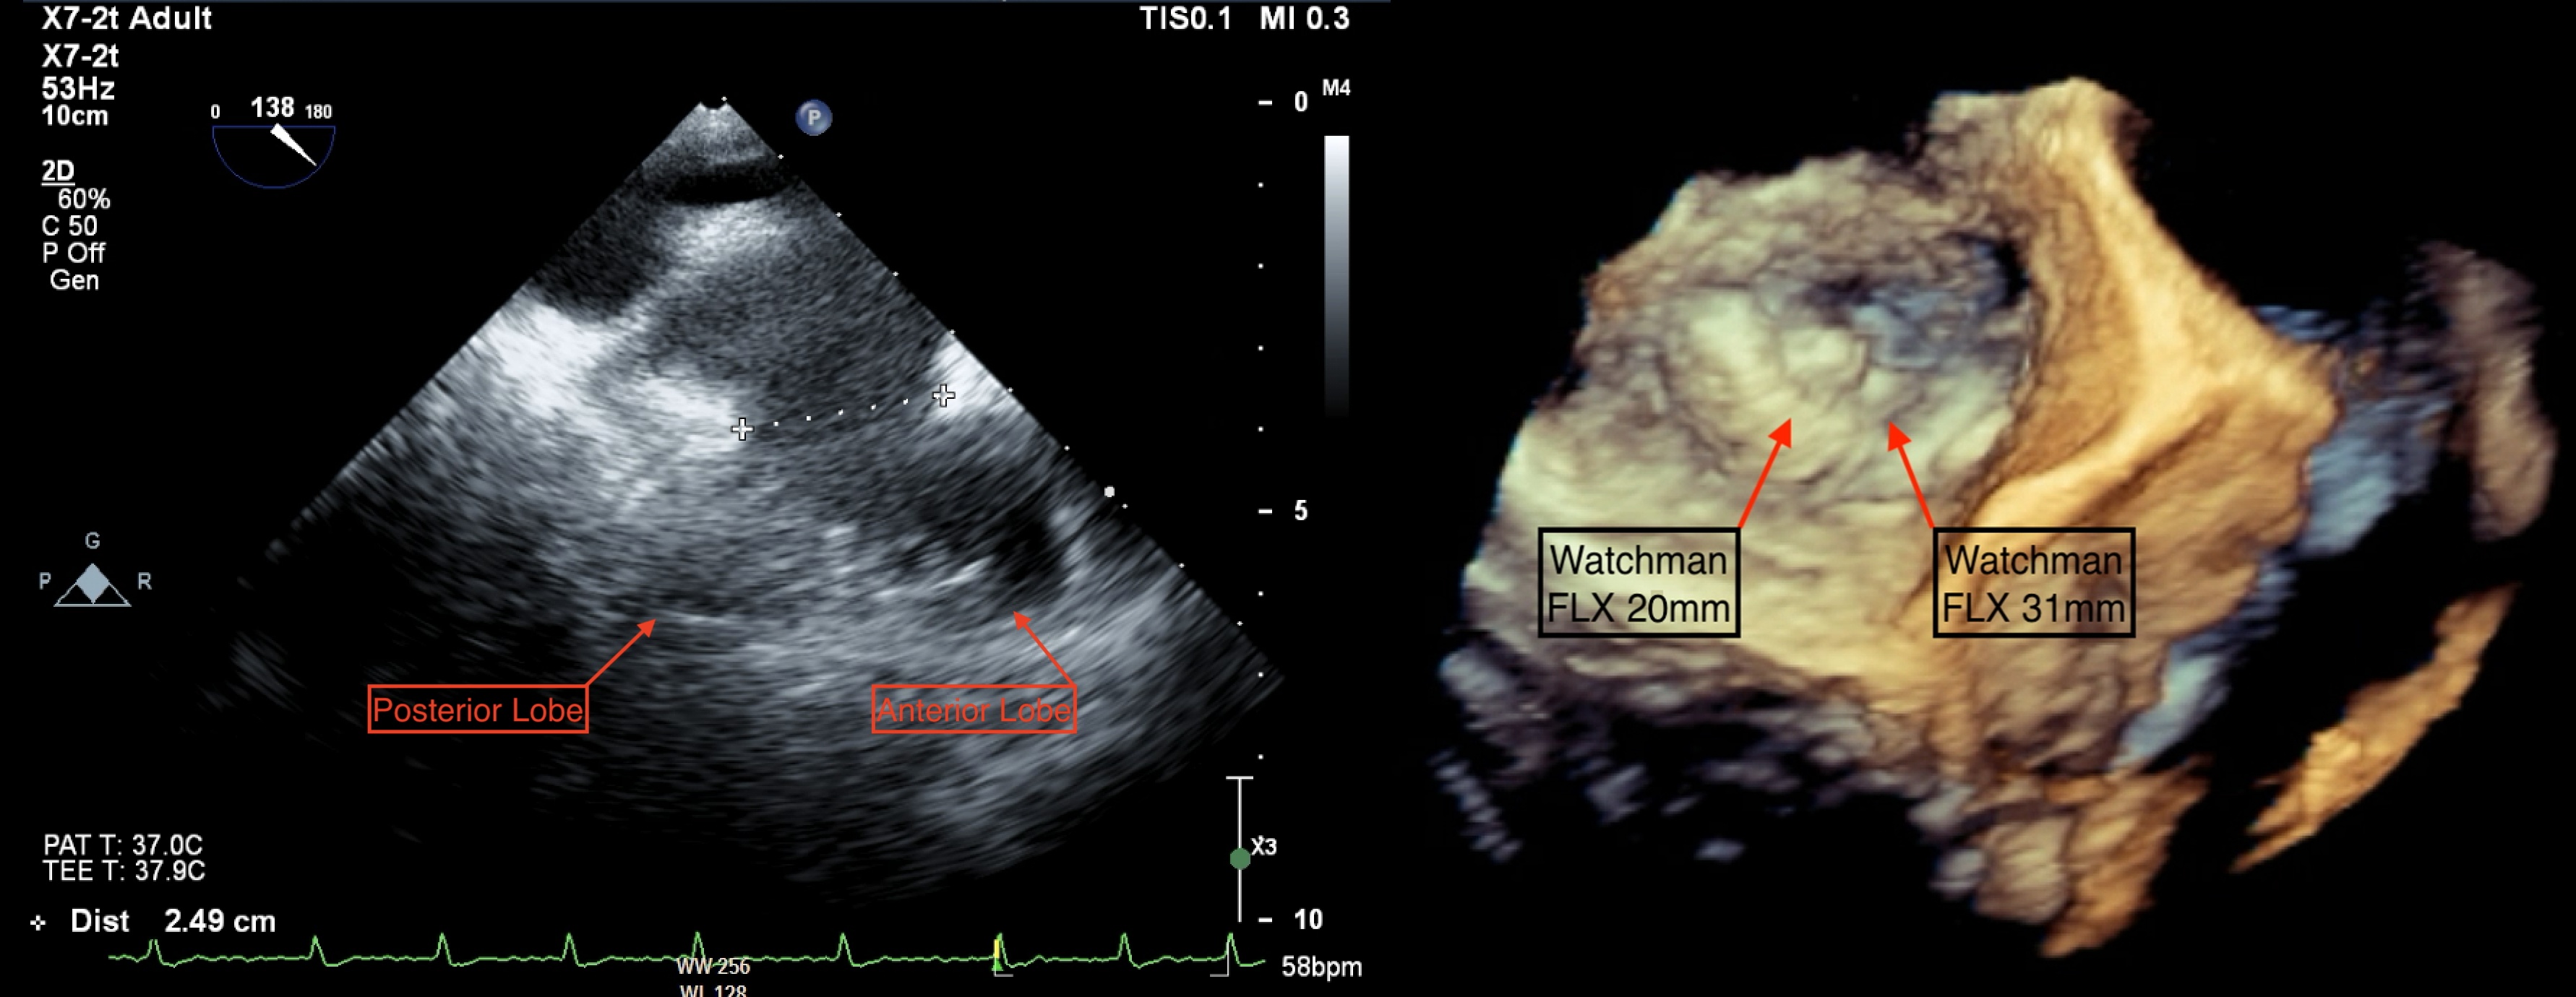

There was no pre-procedure computed tomography as per local protocol. LAA angiography and transoesophageal echocardiography (TOE) revealed a large bilobar LAA (Figure 1A; Video 1) with a maximum ostial diameter of 26 mm. A 31-mm WATCHMAN FLX device (Boston Scientific) was chosen; however, despite multiple device positions, it resulted in complete closure of the anterior lobe and complete patency of the posterior lobe (Video 2).

As there were no suitable alternative devices available, it was decided that a dual device closure strategy would be feasible, given the residual ostial diameter of 10 mm in the posterior lobe. Using a sequential single-sheath strategy, the 31-mm WATCHMAN FLX was deployed in the larger anterior lobe. Subsequently, a 20-mm WATCHMAN FLX was delivered, positioned, and unsheathed on the first attempt. Both devices were stable in a kissing arrangement in the LAA (Figure 2), with reassuring TOE images (Figure 1B).